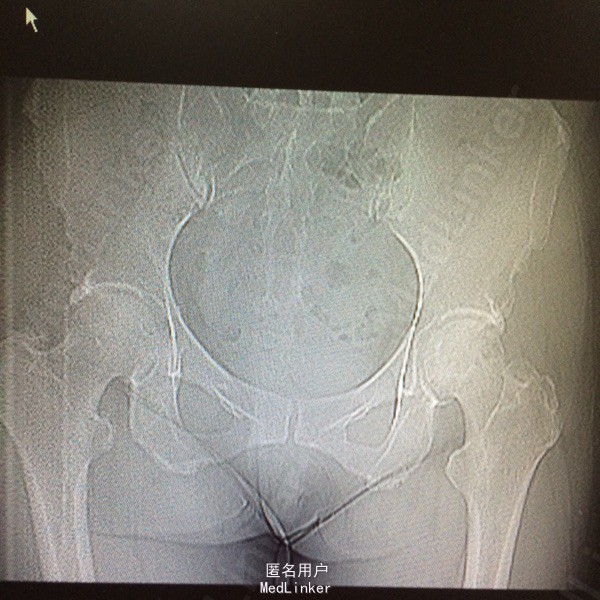

患者,女,50岁。因“双髋关节疼痛活动受限一年余”入院。 患者一年余前无明显诱因感双髋关节疼痛,活动后症状加重,休息后稍有缓解,不伴发热、咳嗽,否认明确外伤史。于今年8月在我院门诊拍片(M00085020)示:双侧股骨缺血性坏死。今为求进一步治疗来我院求诊,门诊查体阅片后以“双侧股骨头缺血性坏死”收住我科。 自起病以来,患者饮食睡眠可,二便正常,体力下降,体重无明显改变。 既往:否认肝肾病史,否认食物、药物过敏史

体格检查:T 36.8℃ P 78次/分 R 20 次/分 BP 142/96mmHg,神志清醒,平静面容,扶拐跛行步入病房,查体合作。发育正常,全身皮肤未见黄染,浅表淋巴结未及肿大,头颅无畸形,双侧瞳孔等大等圆,光反射灵敏。颈软,胸廓无畸形,双肺呼吸音清晰,未闻及干湿性啰音。心律齐,各瓣膜听诊区无杂音。腹平软,无压痛反跳痛,脊柱无畸形,各棘突无压痛。双上肢正常。 专科情况:双髋关节未见明显肿胀,腹股沟中点处深压痛,下肢无轴向叩击痛,双髋关节活动度因疼痛减小,4字征阳性,双足背动脉搏动可及,各趾感觉、活动正常,直腿抬高试验阴性,双下肢无明显短缩。 门诊资料:我院MRI(M00085020)示:“双侧股骨头缺血性坏死”。

初步诊断:双侧股骨头缺血性坏死 鉴别诊断:X线片上未见骨肿瘤,骨囊肿等征象可与肿瘤相相鉴别,具体有待于进一步检查。 诊疗计划:1.卧床休息,暂不负重,对症支持处理。 2.完善相关检查(血、尿分析、肝肾功能、骨盆平片、髋关节CT、胸片ECG、心脏彩超等)。 3.择期手术治疗(髋关节置换术)。